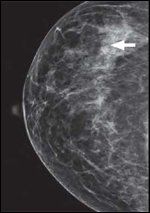

DR. NICOLE KOULANAKIS, surgical oncologist: The patient presented for baseline screening mammogram and was found to have a suspicious area of calcifications in the upper outer quadrant of her right breast (Figures 1 and 2). Stereotactic core needle biopsy revealed pleomorphic lobular carcinoma in situ (LCIS). Her history and physical exam were unremarkable. Family history was significant for two paternal cousins diagnosed with breast cancer in their 50s and a paternal uncle with a “stomach cancer.” The patient underwent a follow-up stereotactic guided biopsy which revealed a 7-mm focus of ER-positive, PR-negative, HER2/neu-negative invasive pleomorphic lobular carcinoma in the setting of diffuse LCIS (Figures 3 and 4). After discussion of her treatment and future cancer-prevention options, the patient elected to undergo bilateral mastectomies, right axillary sentinel lymph node biopsy, and immediate reconstruction. The final pathology demonstrated multiple foci of LCIS present in both mastectomy specimens, and no additional invasive cancer. The sentinel lymph nodes were negative for any metastatic disease.

FIGURE 1

Craniocaudal view of right breast mammogram.FIGURE 2

DR. WENDY HORN: Despite its predominantly occult nature, LCIS has been shown to be associated with mammographic calcifications, and radiologic-pathologic concordance must be established after every biopsy.[3,4] Mammographic findings occur more commonly with the pleomorphic variant of LCIS, given its tendency to undergo comedo necrosis and thus form calcifications.[5] This was the case with our patient: she underwent a stereotactic biopsy for abnormal calcifications found on a screening mammogram, which led to her diagnosis of pleomorphic LCIS.